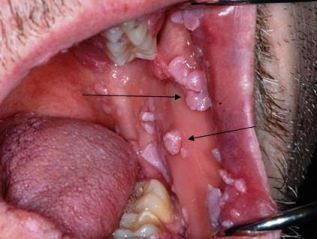

Shown here are condylomata acuminata, associated with human papillomavirus (HPV)-8 and HPV-11; occasionally, infection is caused by HPV-16 and HPV-18. The lesions are usually non-painful and may be solitary or multiple. Lesion color varies from pink to pink-white to white.

Top photo courtesy of Drs Michael Martin and Dolphine Oda; bottom photo courtesy of Dr Tom H. Morton Jr.